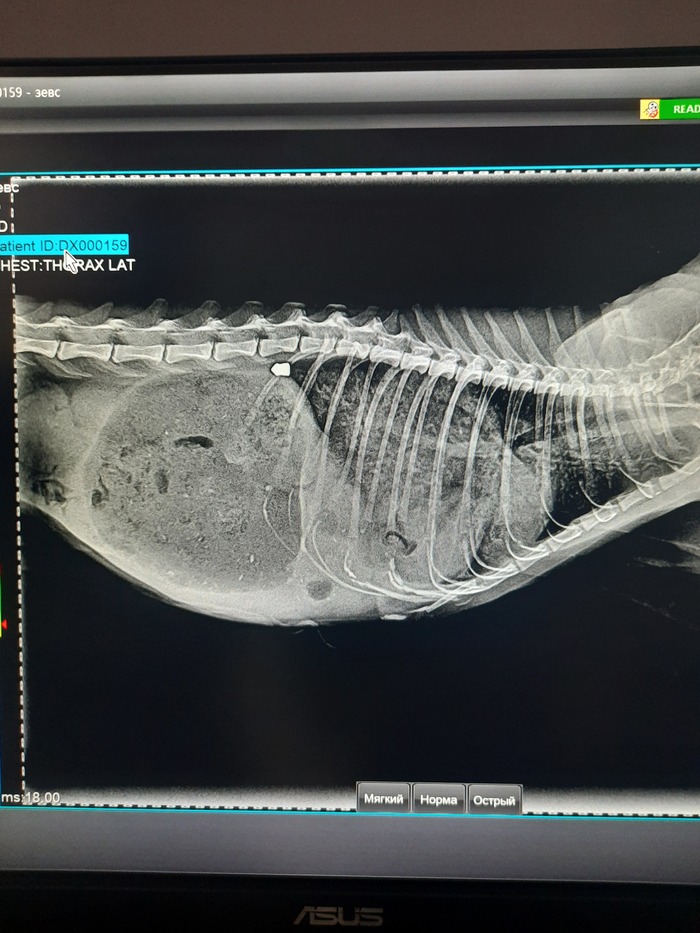

Мы успели. Спасибо просто огромнейшее за оперативность врачам и ассистентам ветклиники Велес. Они мгновенно взяли кота, сделали узи, поставили катетер, сделали рентген и посадили в бокс на кислород.

У кота застрявшая пуля под позвоночником. Свежая она или нет, пока непонятно.

У кота пробито и сдулось одно лёгкое, с правой стороны, разрыв диафрагмы и выпад кишечника в грудную полость.

Связанно это с пулей или нет, тоже пока непонятно.

По анализам кот как-будто месяц не ел...

Врач не исключает и абсцесса внутри, тк лейкоциты за 40тыщ улетели...

По задним конечностям претензий нет, рентген показал все кости целы!